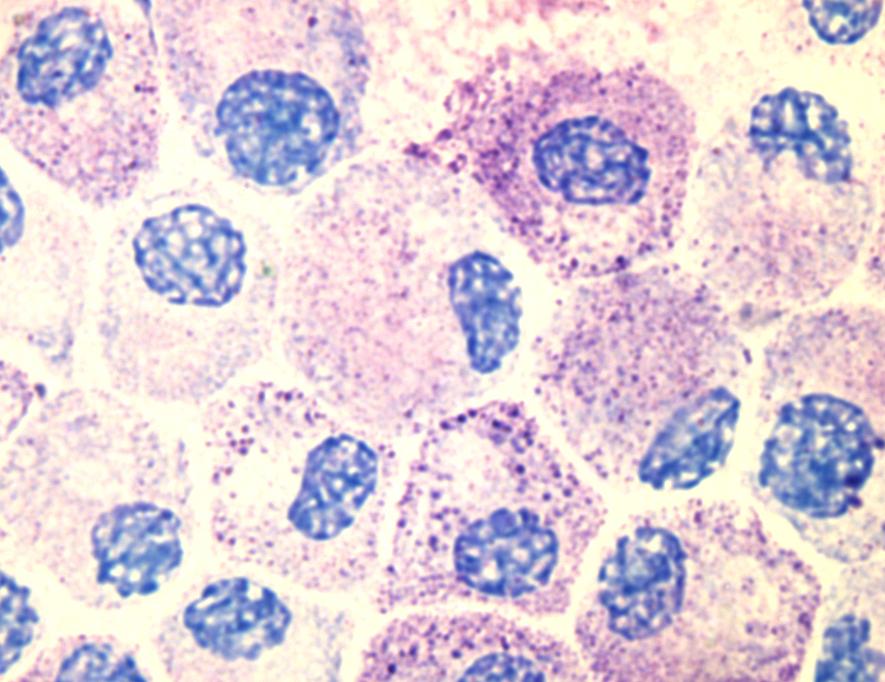

Mense, Simons, Russel noted that spot tenderness of both TrPs and nodules would be the result of sensitized nociceptors. The nociceptors are most likely sensitized by substances released as a result of the local energy crisis and tissue distress, which apparently are associated with these histopathologic changes and endplate dysfunction. Bradykinin is an effective sensitizing agent that is released in hypoxic or ischemic tissue. (Muscle Pain: Understanding Its Nature, Diagnosis, and Treatment By Siegfried Mense, David G. Simons, I. Jon Russell )

Mense, Simons, Russel noted that spot tenderness of both MFTPs and nodules would be the result of sensitized nociceptors. The nociceptors are most likely sensitized by substances released as a result of the local energy crisis and tissue distress, which apparently are associated with these histopathologic changes and endplate dysfunction. Bradykinin is an effective sensitizing agent that is released in hypoxic or ischemic tissue. (Muscle Pain: Understanding Its Nature, Diagnosis, and Treatment By Siegfried Mense, David G. Simons, I. Jon Russell)

As the muscles withdraw from injury (inflammatory chemicals) palpated musculature will display a twitch response. Myofascial Trigger Points (MFTPs) are hyper-irritable spots in skeletal muscle associated with palpable nodules in the taut bands of muscle fibres. When these palpable nodules are stimulated mechanically, local pain and referred pain can be induced together with visible local twitch response.